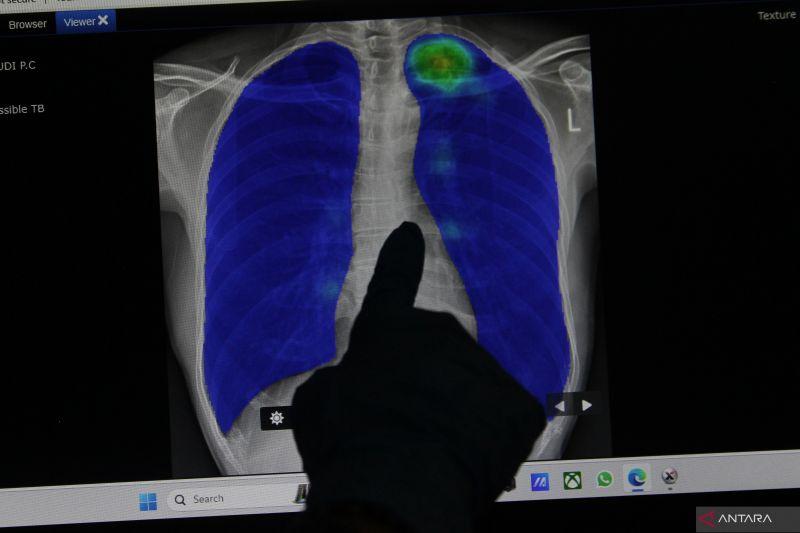

Jika hasil pemeriksaan menunjukkan adanya infeksi pada paru-paru, ia melanjutkan, pasien harus rutin periksa dan menjalani pengeluaran cairan guna memastikan tidak ada tumor atau kanker pada paru-parunya.

Dia menyarankan pemeriksaan jantung dan paru-paru untuk mendeteksi kemungkinan mengalami paru-paru basah atau infeksi lainnya.